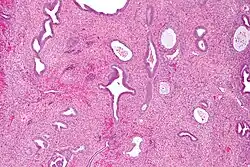

Endometrial polyps can be solitary or occur with others.[11] They are round or oval and measure between a few millimeters and several centimeters in diameter.[7][11] They are usually the same red/brown color of the surrounding endometrium although large ones can appear to be a darker red.[7] The polyps consist of dense, fibrous tissue (stroma), blood vessels and glandlike spaces lined with endometrial epithelium.[7] If they are pedunculated, they are attached by a thin stalk (pedicle). If they are sessile, they are connected by a flat base to the uterine wall.[11] Pedunculated polyps are more common than sessile ones.[4]